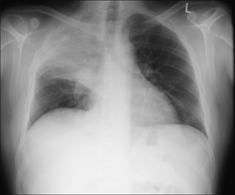

Figure 30.6 Mild haemoptysis. Due to infection. Lobar pneumonia.